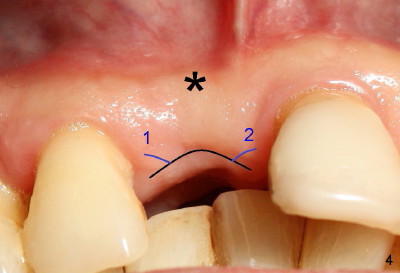

Fig.4-7 show modified semilunar incision helps form cosmetically-pleasing attached gingiva. Prior to uncover, the buccal plate of #8 (*) is concave, as compared to those of the neighboring teeth. The main incision is indicated by black line, lingual to the crest so that the buccal flap is more bulky. It is curved and festooned to create the future cosmetic buccal gingival margin. If the main incision is placed too lingual to expose the implant, one or two accessory incisions (red) can be made. After insertion of 4x6.5 mm non-shouldered abutment 3 mm post, PVS impression is taken. Fig.5 shows temporary crown in place (T) with two vertical mattress suture in the mesial and distal papillae. Two accessory incisions are approximated. The attached gingiva over the temporary crown immediately becomes bulky (*). Two weeks later, the temporary crown is removed. The accessory incision #1 has healed, while #2 is healing (Fig.6). The temporary crown helps form a nice socket around the abutment (A). The buccal attached gingiva (*) is leveling with that of the neighboring teeth, as compared to concavity before uncover (Fig.4). Fig.7 shows the gingiva around the crown (to be cemented) with healing incision #2. The buccal attached gingiva(*) is as bulky as immediately after uncover (Fig.5). Return to original article